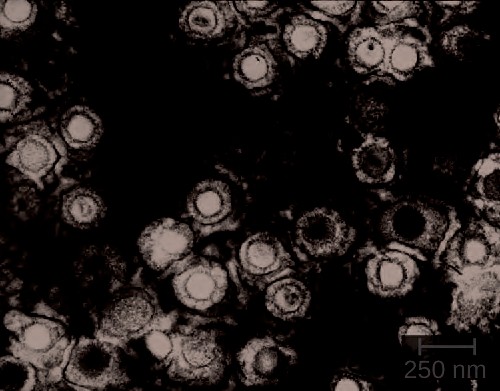

Genital herpes is a common condition caused by the herpes simplex virus (Figure 23.16), an enveloped, double- stranded DNA virus that is classified into two distinct types. Herpes simplex virus has several virulence factors, including infected cell protein (ICP) 34.5, which helps in replication and inhibits the maturation of dendritic cells as a mechanism of avoiding elimination by the immune system. In addition, surface glycoproteins on the viral envelope promote the coating of herpes simplex virus with antibodies and complement factors, allowing the virus to appear as “self” and prevent immune system activation and elimination.

Figure 23.16 Virions of the herpes simplex virus are shown here in this transmission electron micrograph. (credit: modification of work by Centers for Disease Control and Prevention)